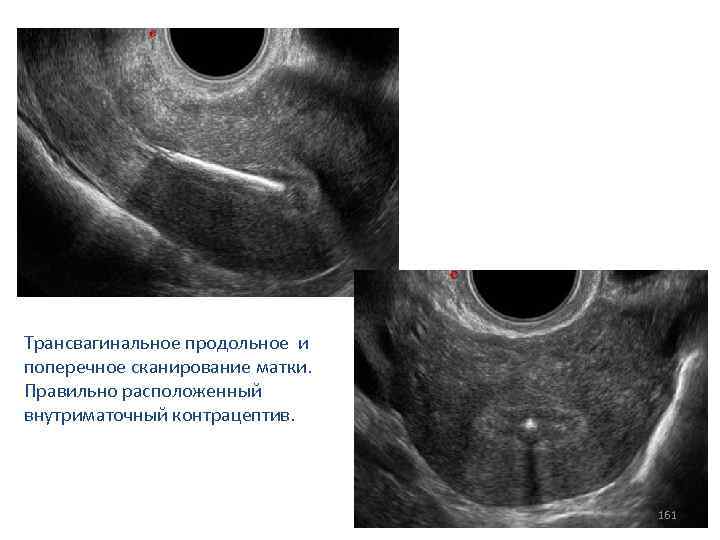

Трансвагинальное продольное и поперечное сканирование матки. Правильно расположенный внутриматочный контрацептив. 161